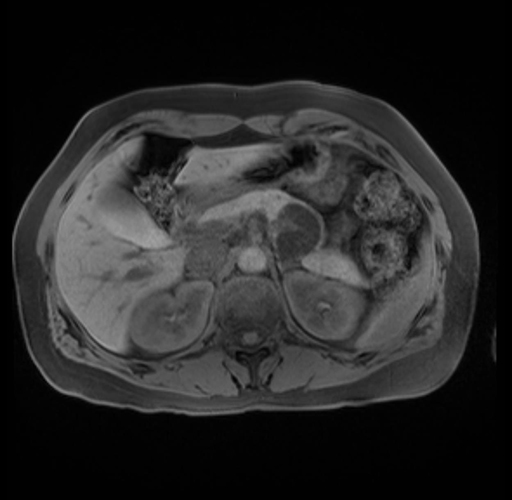

Laparoscopic distal pancreatectomy with possible splenectomy [case 14]

Imaging Analysis

Look through the patient's CT scan to identify any areas of concern for the necessary procedure.

Based on your CT findings, which issue(s) are present and would give reason for "planned slowing down moment(s)" in this case?

Considering a standard distal pancreatectomy procedure, what step(s) of the operation would you do differently in this case?